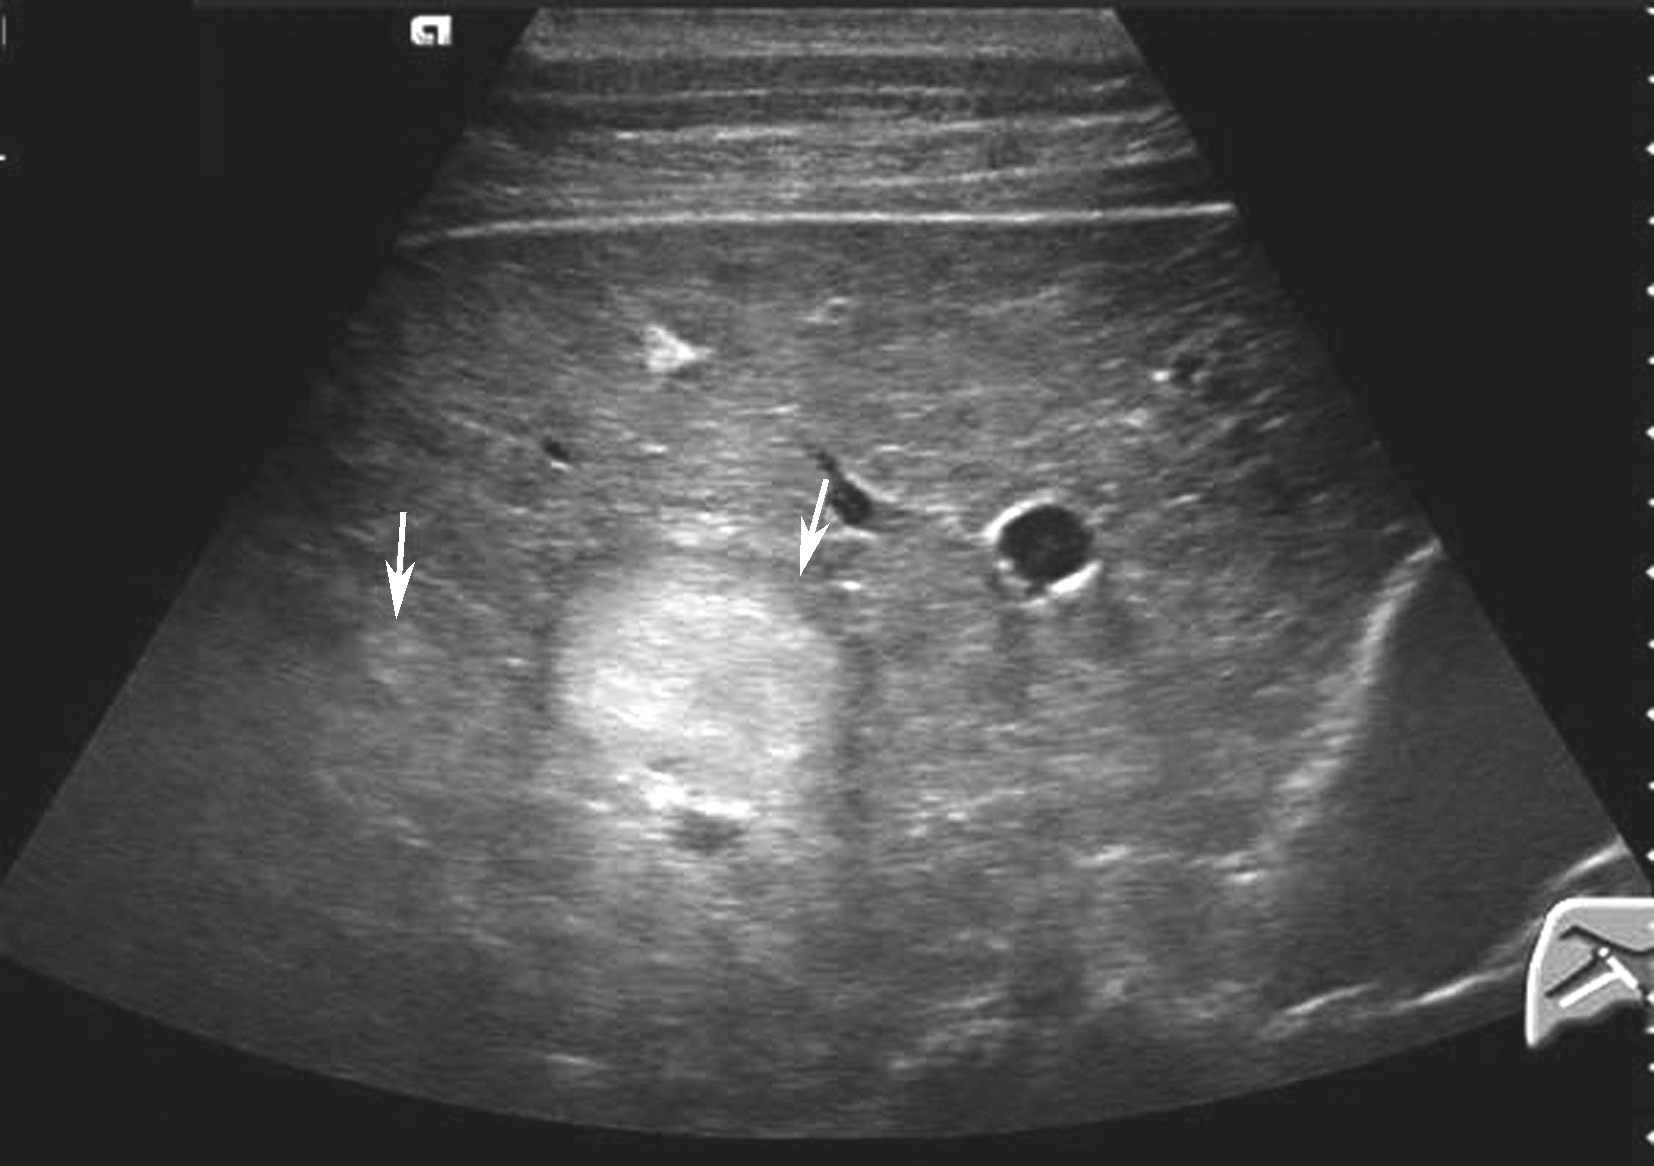

【声像图表现】

(1)二维灰阶图像:

典型的肝血管瘤二维超声图像为均一的高回声,通常直径小于3cm,圆形或卵圆形,边界清晰,周围无晕环,可位于肝血管旁,仔细查看结节内部有筛网状的结构,运用高频探头探查可见瘤体与肝组织间有小血管的管道相通。有的肝血管瘤后方可有增强(可能系内部丰富血窦血液所致)。在脂肪肝背景下,肝血管瘤可表现为低回声,边界清晰、规则,外周可有相对较厚的带状高回声环绕,厚度较为均匀,其内也可见不规则“等号”状血管断面回声,当其位于瘤体边缘时可形成所谓的“边缘裂隙征”,瘤体后方回声稍增强;直径大于5cm的较大海绵状血管瘤多呈混合性回声,周围可见线状高回声环绕,可不完整或厚薄不甚一致,瘤体内可见低回声、高回声及不规则无回声区混合存在。瘤体内部回声的强弱,是瘤内血管腔、血管壁及血管间隙之间纤维隔的多少和薄厚的综合回声特征。若瘤内血窦较大或丰富时,瘤体后方回声可轻度增强。若血管内产生血栓、纤维化、钙化等改变,则内部回声更为复杂。肝血管瘤二维灰阶图像如图5-21-12所示。

图5-21-12 肝血管瘤二维灰阶图像

(2)彩色多普勒超声:

尽管血管瘤内血管丰富,但血流速度极为缓慢,彩色多普勒可显示部分血管瘤内部或周边的斑状或短线状血管,频谱均为低速血流。对小血管瘤,尤其位于肝脏深部者则难以检测到血流信号。

(3)超声造影表现:

血管瘤典型的超声造影表现为:动脉相周边结节样或环状高回声增强,门静脉相和延迟相造影剂进行性向心性填充,填充可以是完全性的或部分性,60%~80%的肝血管瘤表现为这一典型特征。造影剂填充的速度根据血管瘤的大小而不同,小血管瘤只需1min,大的可能需要10min。20%~30%肝血管瘤内含有丰富的动静脉短路,充填时间会减短到1min甚至几秒,因此造影后的60秒内观察肝血管瘤的增强特征是非常重要的。如果瘤内有纤维化或栓塞,造影剂填充不完全,这种情况也可能发生在较小的血管瘤。如果有典型的造影增强行为可以诊断血管瘤,而不需进一步其他影像检查。肝血管瘤超声造影动脉期、静脉期及延迟期超声声像图表现如图5-21-13~图5-21-15所示。